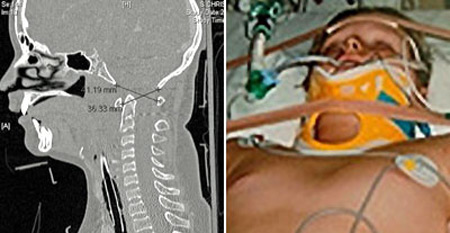

قام الاطباء بتثبيت رقبته إلى جسده بالمسامير |

وقال الأطباء المعالجون للمراهق البالغ من العمر حاليا 14 عاما إن النجاة مثل هذا النوع من الإصابات نادرة جدا وان التعافي منها بشكل كامل هو أمر أكثر ندرة لكنه حصل مع هذا المراهق.

وعقب حصول الحادث في أواخر العام 2006، قام الأطباء بإخضاع الصبي المصاب إلى عملية جراحية عاجلة استمرت لمدة 7 ساعات، وهي العملية التي نجحوا خلالها في إعادة تثبيت فقرات رقبته وتوصيلها إلى قاعدة الجمجمة باستخدام مسامير وشرائح مصنوعة من معدن التيتانيوم.

وقال الأطباء أن أفضل ما كانوا يتوقعونه هو أن يبقى الصبي على قيد الحياة، لكن حالته شهدت تحسنا ملموسا واستمر في التعافي من إصابته بشكل مذهل إلى أن عاد أخيرا إلى مزاولة رياضة سباقات السيارات.